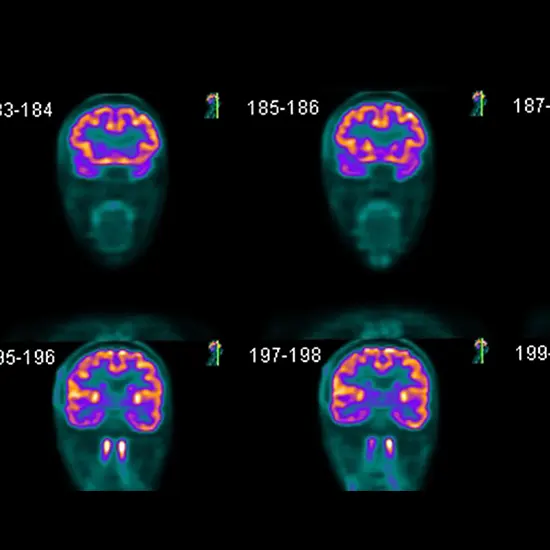

See Inside The Mind With Clarity - Brain PET Scan.

4. Imaging: The affected person will then be located on a desk that slides into a PET CT scanner. The scanner will take pix of the brain, which will exhibit the distribution of the tracer in the brain.

5. CT scan: The CT component of the examination entails taking pictures of the Genius and the usage of X-rays. The CT pics will be used to grant a specified view of the brain's anatomy, whilst the PET pix will exhibit the distribution of the tracer in the brain.